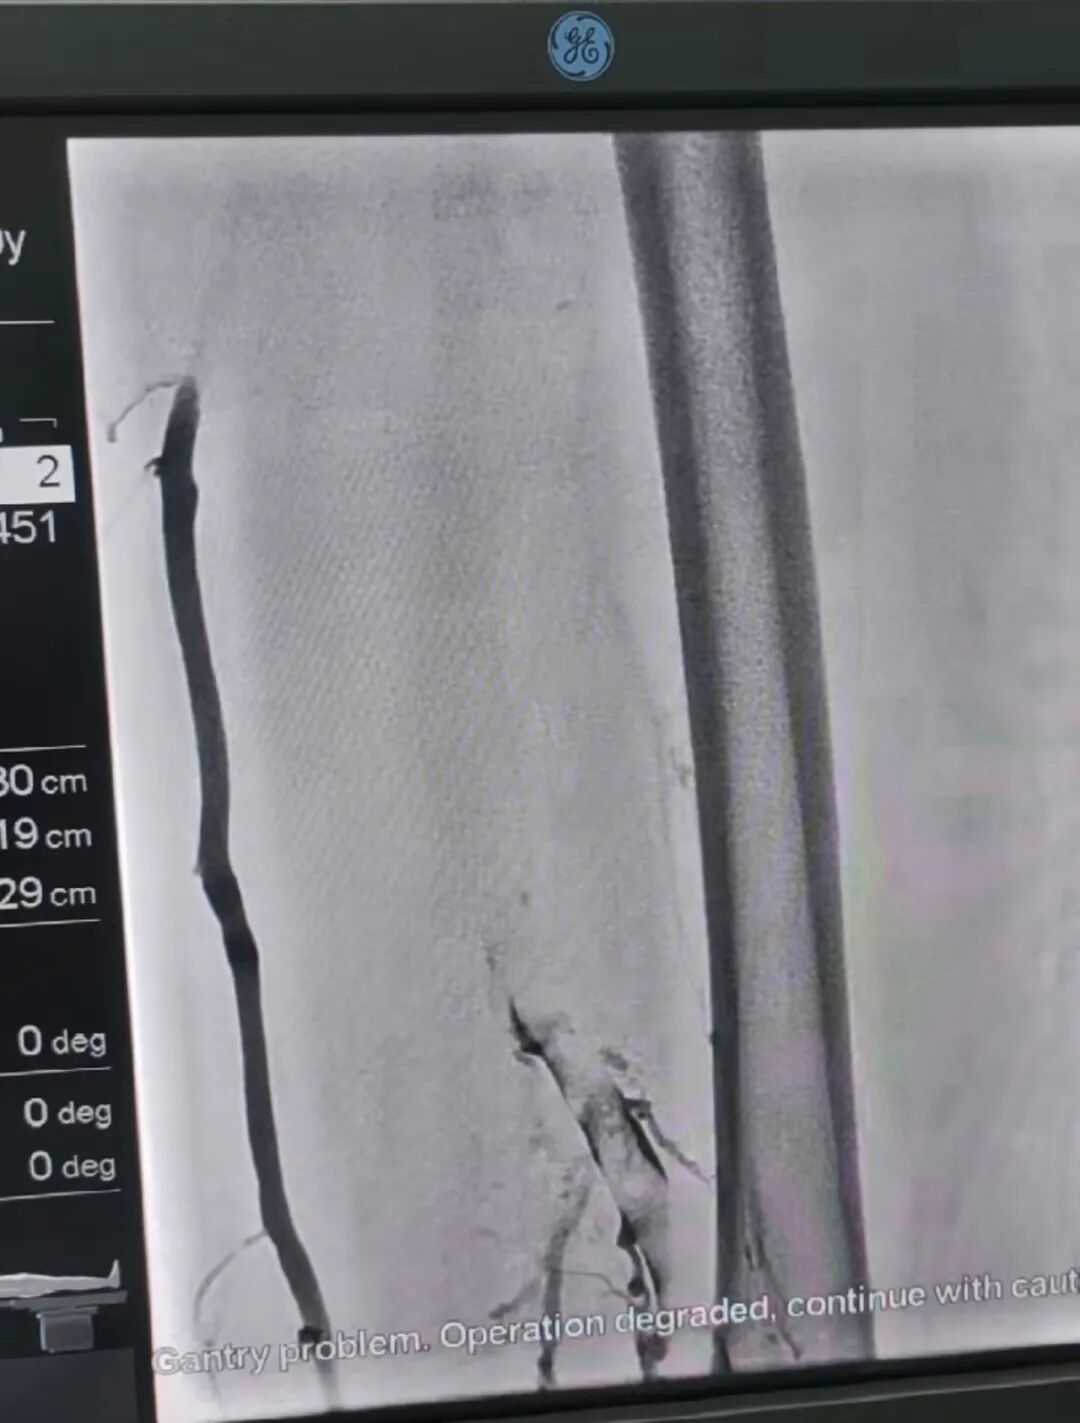

• 字体

据悉,该患者因左下肢突发肿胀、活动受限来院就诊,结合既往病例和医院检查结果最终诊断为左下肢深静脉血栓形成,血管闭塞导致血液回流受阻,若不及时干预,可能引发肺栓塞等致命并发症,还可能导致慢性水肿、皮肤色素沉着等远期后遗症。面对复杂病情,脑病中心介入团队进行充分讨论研究,最终决定采用多术式联合的微创介入疗法治疗方案,兼顾血栓清除、风险预防与血管功能修复。

术中,脑病中心介入团队先是通过微创穿刺置入下肢静脉滤器,构建肺栓塞防护屏障,有效阻挡血栓脱落引发的致命风险;随后精准实施静脉取栓术,彻底清除血管内阻塞血栓,恢复血流通道;最后采用球囊扩张术对狭窄血管段进行扩张塑形及支架植入支撑狭窄改善血管通畅性,降低血栓复发概率,同时减少患者长期抗凝药物的用量负担。整个手术花费10多个小时,历经4次手术,全程微创,仅通过局部穿刺完成,具有出血少、恢复快、创伤小的优势。术后患者左下肢肿胀迅速消退,肢体功能逐步恢复,目前已顺利康复出院。